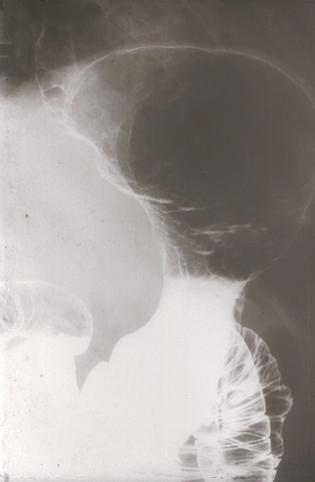

clasificación del pacienteTumor Maligno del Sistema Linfático/Linfoma Maligno

parte(separada por órganos)estómago(región)/mas de dos

método de exámenRayos X

diámetro mayor del tumor10 - 14

grado de penetraciónsm